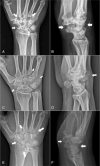

Patient concerns: All 3 cases were examined between January 2016 and December 2019. Three patients presented with similar clinical manifestations and radiographic features, with multiple osteolytic lesions in the carpal bones and metacarpal bone base.

Diagnoses: The 3 cases were diagnosed as diffuse type tenosynovial giant cell tumor, calcifying aponeurotic fibroma, and rheumatoid arthritis.